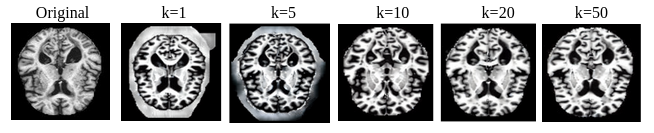

Refer to caption

Figure 1: Comparison of LLCM different steps generated medical images of (512×\times×512) resolution in different inference steps against original images.

Our research aims to bridge this gap by introducing a novel contribution to the field. We propose the creation of the MedImgs dataset, which contains a wide range of medical images of both humans and animals. This dataset is designed to provide a comprehensive resource for training and evaluating deep learning models in the medical domain. Additionally, we introduce the leapfrog latent consistency model (LLCM), which utilizes the Leapfrog solver, an efficient and rapid PF-ODE solver, to generate high-resolution images (512×\times×512) in as few as 1-4 inference steps. These advancements not only address the data scarcity issue but also enhance the performance of deep learning models in medical imaging, paving the way for more accurate and accessible AI-driven medical solutions.